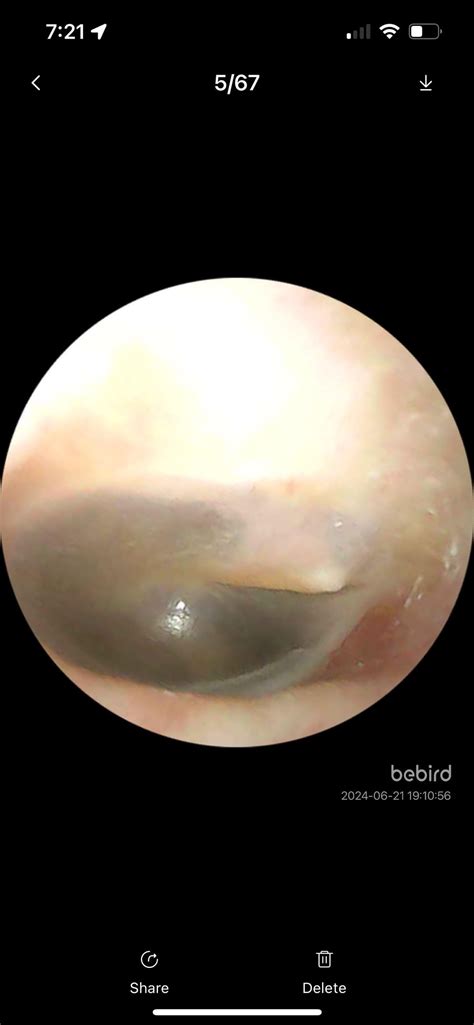

Bulge In Eardrum

Ear health is a critical aspect of overall well-being, and one condition that can significantly impact it is a bulge in the eardrum. This condition, also known as a tympanic membrane bulge, occurs when the eardrum protrudes outward from its normal position. Understanding the causes, symptoms, and treatment options for a bulge in the eardrum is essential for maintaining good ear health.

Diagnosing a Bulge in the Eardrum

• Otoscopy: Using an otoscope to examine the ear canal and eardrum.